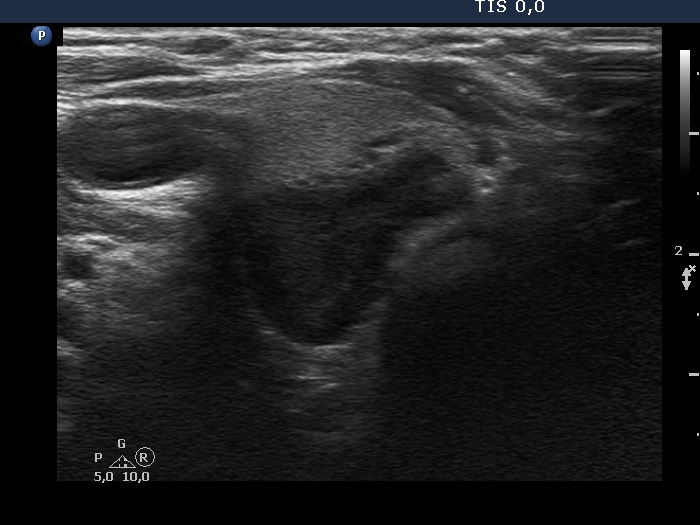

Lower part of the right lobe, transverse scan. There is a hypoechoic nodule dorsal to the isoechoic lesion.